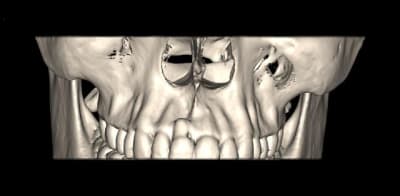

Tu n’a pas un couloir suffisent entre les corticales pour placer un implant avec des vis à compression ?

Sinon concernant ton cas j'ai l'impression qu'il y a de l'os en mesial et distal de ta dent du coup si c'est bien le cas je ferais de la rog avec une membrane pinsee